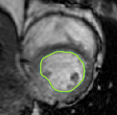

4.2 Visual assessment

We select the case that achieves the highest and lowest dice score for visual assessment. Fig. 4 shows example segmentation results where the proposed method achieved the highest agreement with the ground truth delineations. Fig. 5 shows example segmentation results where the proposed method achieved the lowest agreement with the ground truth delineations.